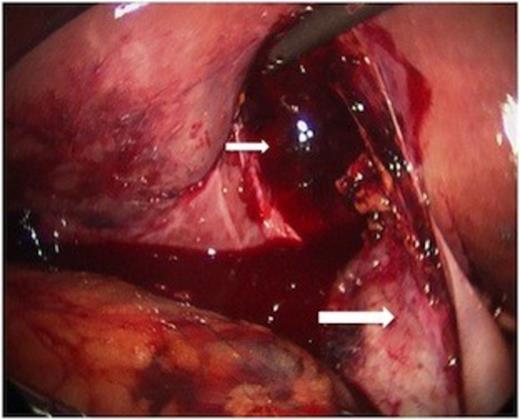

While hepatic contrast extravasation in a stable patient is typically treated with angioembolization, proximity to the gallbladder was concerning for gallbladder injury. Exploratory laparoscopy was performed and the gallbladder was found to be perforated and nearly completely avulsed from the liver (Figures 2 and 3).

At laparoscopy, the gallbladder (large white arrow) was found partially avulsed from the gallbladder fossa (small white arrow).

The body of the gallbladder was perforated on its inferior surface (arrow).

Minimal additional blunt dissection exposed the cystic artery and duct. A critical view of safety was achieved so that cholecystectomy could be performed. Only a small amount of oozing was noted from the liver laceration, following removal of the gallbladder. Haemostasis was achieved with topical agents. The pathologic specimen showed acute inflammation with perforation (Figure 4).